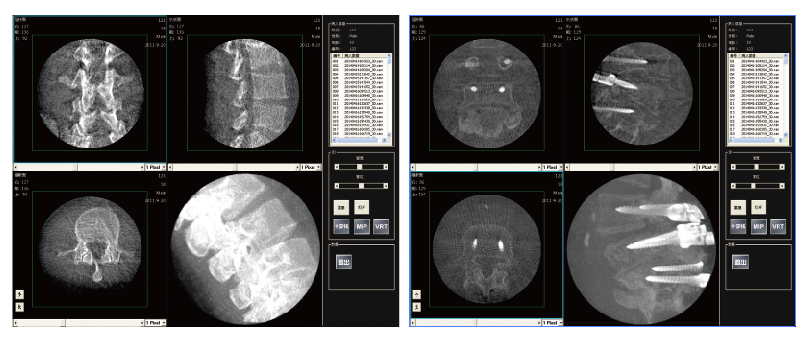

PLX7200三維C形臂骨科手術應用

2、植入物位置更加準確,確保手術安全,提高手術的效果。

3、通過一次多角度自動采集,既可獲得全面、準確的影像信息,減少重復采strdfgwgl集次數,投照劑量和手術時間也相應減少。

4、在手術結束之前使用,在手術室既可以完成三維評估,準確地檢測定位誤差并及時進行修正,不再需要術后移至CT室進行復查,減少因錯位等原因進行二次手術的可能。